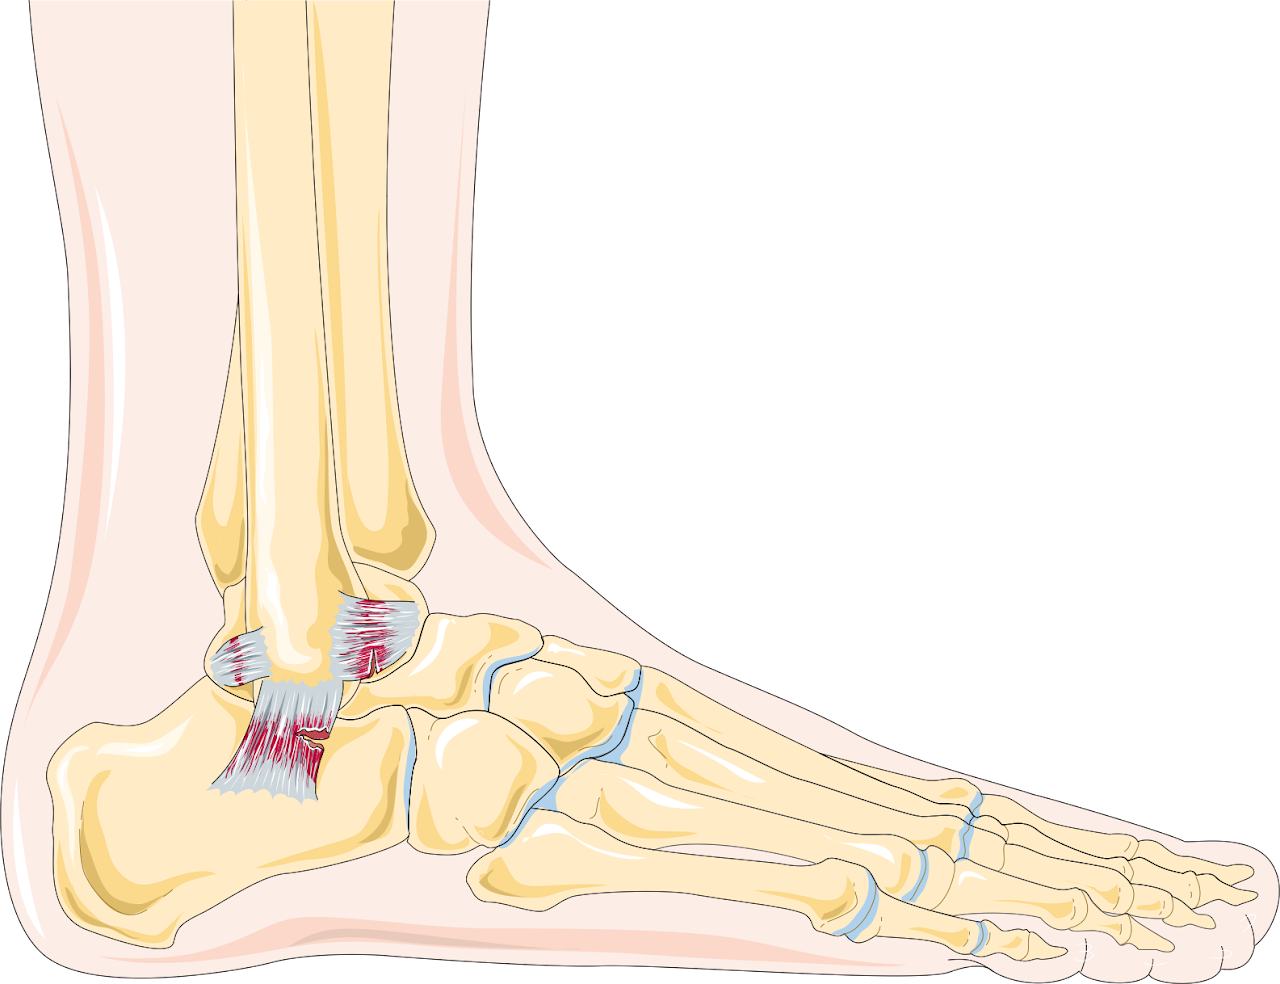

Ankle Sprains

Injuries to the ligaments around the ankle. Treatments include rest, ice, compression, elevation (RICE), and physical therapy.